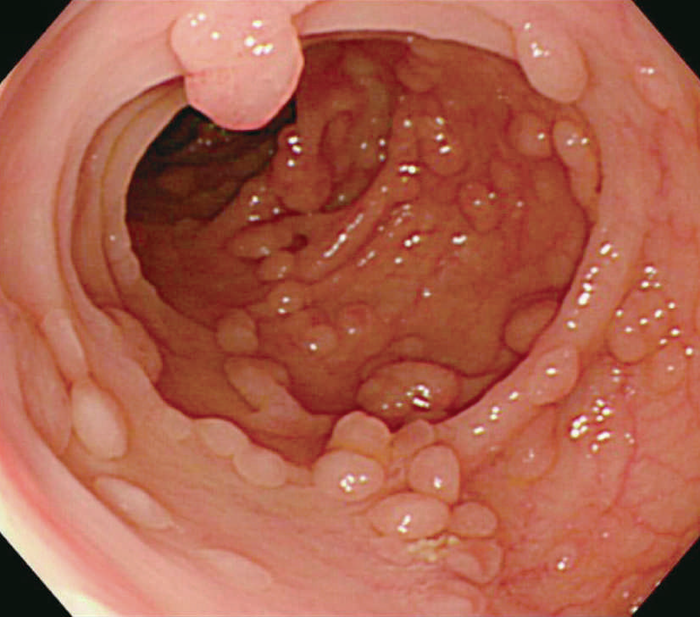

- 古典型FAPは数百から数千の大腸腺腫性ポリープを特徴とし,平均16歳(範囲7~36歳)から発症し始める。古典型FAPの場合,95%が35歳までにポリープを形成し,大腸切除などの介入を行わなければCRCは避けられない。未治療者のCRC診断の平均年齢は39歳(範囲34~43歳)である。古典型FAPは腺腫密度により,密生型FAP,非密生型FAPに分類されることがあり,肉眼的に正常粘膜が観察できないほど腺腫を発生し,腺腫数が>1,000個(または>2,000個)の場合,密生型FAP(severe/profuse/dense FAP)(図Ⅱ-1),正常粘膜を背景に腺腫が多発し腺腫数がおよそ100~1,000個(または2,000個)の場合,非密生型FAP(sparse FAP)と分類する(図Ⅱ-2)ことがある。ただし,大腸の部位によって腺腫密度が異なることもしばしば経験し,密生型と非密生型を厳密に区別する臨床的意義は乏しい。

図Ⅱ-2 非密生型FAP